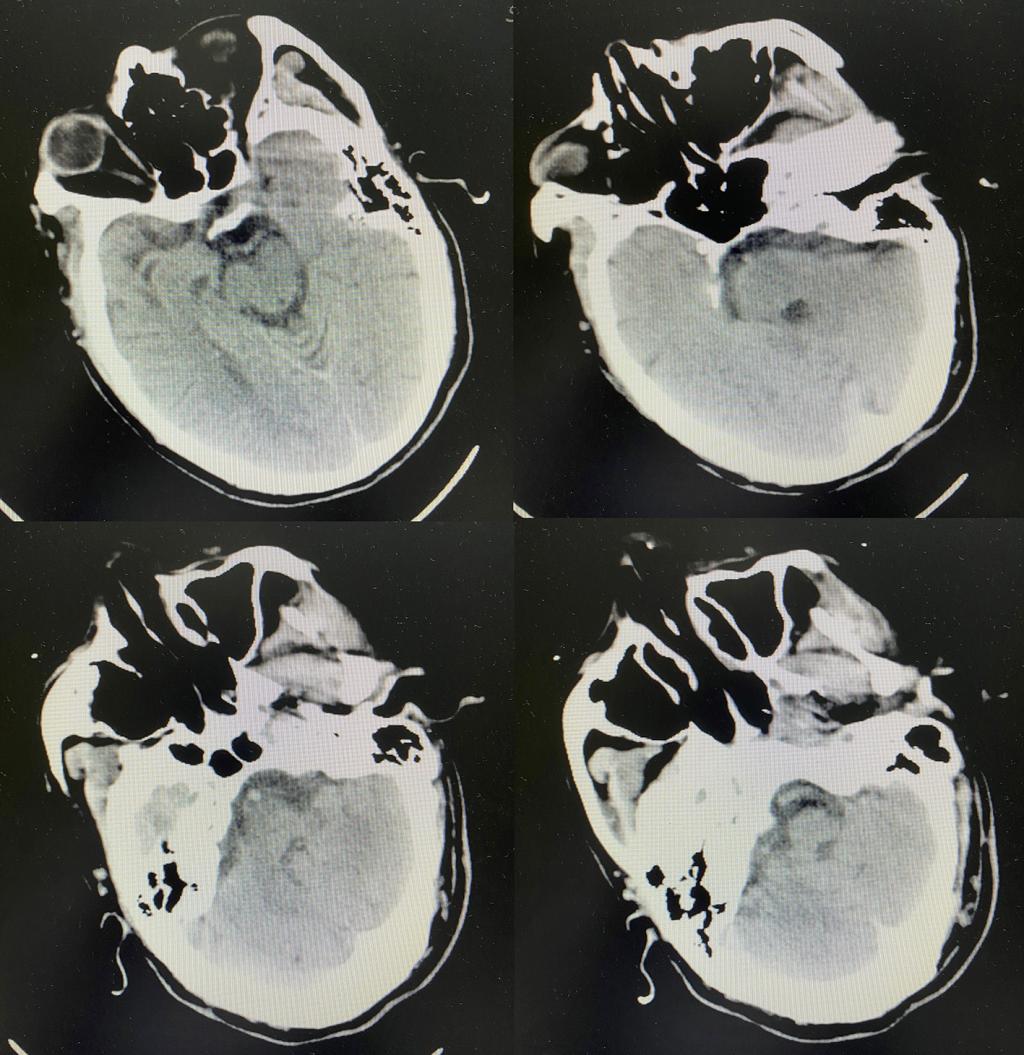

识别卒中早一秒 挽救大脑恢复好——神经内科桥接取栓显奇效

近日,神经内科介入团队为一位院内卒中患者桥接取栓,及时挽救了患者生命。 10月28日晚,神经内科病房内,值班医生正在巡视住院患者。突然传来一声“不好了,患者吐啦,医生快来”的呼救打破了病房的平静,原来是一位下午刚因头晕收治的患者突发不适。...